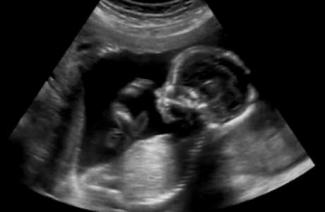

DeAnnin príbeh nám pripomína, že žiadna situácia nie je beznádejná. Aj keď okolnosti jej [života] vyzerali ponuro a zúfalo, súcitný personál v jednom tehotenskom centre Online for Life´s pomohol DeAnne spoznať, že neplánované tehotenstvo neznamená koniec jej snov. „Všetci moji priatelia mi hovorili, čo všetko už viac nemôžem robiť... ale táto dáma... ona ma jednoducho ďalej povzbudzovala a hovorila mi o všetkom, čo môžem robiť aj naďalej,“ hovorí DeAnna opisujúc ošetrovateľku tohto tehotenská centra; ošetrovateľku, ktorá sa zastala života.

Teraz má DeAnna krásneho chlapčeka, ktorý je svetlom jej života. „Stále mám svoje sny. Budem sa musieť len viac snažiť, aby som ich dosiahla,“ hovorí s očakávaním.